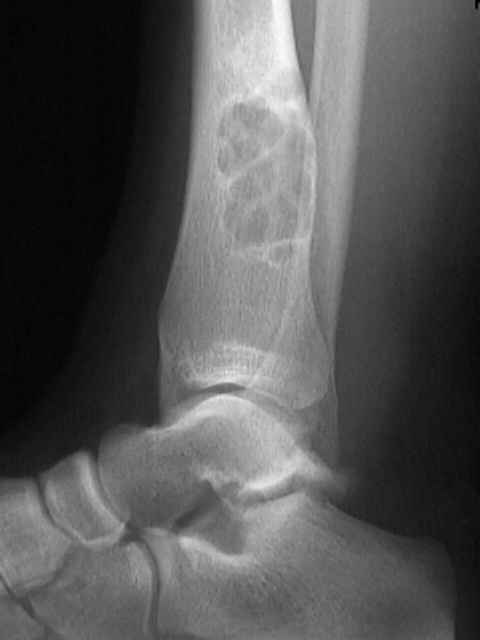

El fibroma no osificante normalmente es excéntrico en su situación (figura1) esta lesión involucra más a menudo el canal medular y la corteza subyacente. Se presenta como un defecto radiolucente elíptico, Se localiza en la metáfisis o el área metadiafisaria y exhibe un modelo de crecimiento longitudinal. Los bordes exteriores de la lesión son lobulados, semejando un racimo de uvas (figura2). La arquitectura interior tiene una apariencia espumosa. Hay normalmente una corteza de hueso reactivo o esclerosis que rodean la lesión; puede haber adelgazamiento cortical y en algún caso ligera expansión, que puede mal interpretarse como un cambio maligno (figura 3). No hay reacción perióstica a menos que haya una fractura patológica.

El tamaño varía de 0.5 hasta 7 cm. Existen varios estadios intermedios. las pequeñas lesiones corticales o subperiósticas se presentan como una excavación en la cortical (Entonces se llaman defecto fibroso cortical) y las lesiones más grandes (que se llaman fibroma no osteogénico o defecto fibroso metafisario), y generalmente se reconoce que básicamente son diferentes manifestaciones de un mismo proceso. Su eje más largo está alineado con el eje longitudinal del hueso afecto. Muchos focos experimentan una involución espontánea (curación) por un proceso de remodelación del hueso tubular con una disminución del diámetro de la diáfisis, resultando finalmente en una osteoesclerosis. Unas pocas lesiones pueden continuar creciendo y extenderse hasta la la cavidad medular y muestran un borde esclerótico festoneado que se localiza excéntricamente en el hueso.

La lesión normalmente se desarrolla en la metáfisis del fémur distal (90% de  los casos) la tibia distal, y  excéntricamente.

Localizada dentro de o adyacente a la cortical.

Puede localizarse excéntricamente dentro de la cavidad medular.

La cortical puede abombarse sobre la lesión, como falta de remodelación.

Puede rodearse por un margen delgado bien definido de hueso reactivo.

No se ve ninguna reacción perióstica a menos que haya habido una fractura.